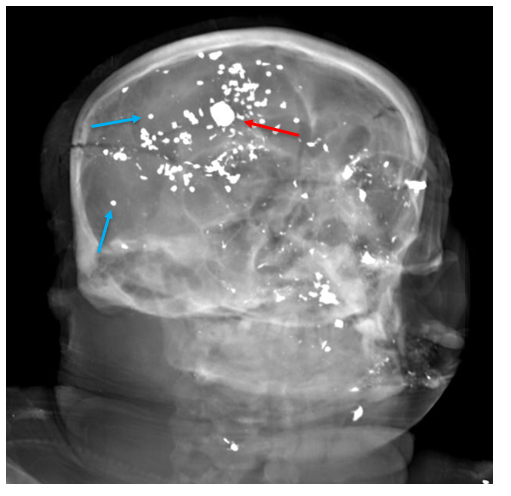

In the first pathway, consider an autopsy of a person with a single gunshot wound to the head. In a readily accessible region like the temple or beneath the chin, this wound could easily be self-inflicted. While this would be a “typical” location for a suicidal injury, such a wound could also be inflicted by another person. There are indicators we look for at autopsy which favor one scenario over the other. For example, most suicidal gunshot wounds (broadly speaking, of course) are contact wounds or intra-oral. A self-inflicted gunshot wound to the back of the head would be unusual, but (contrary to popular conception), not impossible depending on the firearm used. However, the same type of pattern could be elicited with another person holding a firearm to that individual’s head. We may examine the length of the firearm to determine if it’s possible for the decedent to have pulled the trigger themselves (keeping in mind that other items like a cane, coat hanger, or even the decedent’s toe, may have been used to depress the trigger). Similar questions can arise in autopsies of people who have fallen from height. There is no way an autopsy can tell with certainty whether an individual was pushed, fell accidentally, or left the edge of an elevated structure intentionally. The cause of death in both situations is undisputed – a gunshot wound in the first, and blunt force injuries in the second. This is why contextual information, like scene photographs and investigative records, is indispensable for forensic pathologists. Without context, we have no way to discern homicides, suicides, and accidents. Occasionally even with context, there can be competing narratives (one witness claims a gunshot wound was self-inflicted, while another claims it was inflicted by the first) or suspicious circumstances to cast doubt. Without clear cut evidence to support one story, the manner of undetermined is appropriate.

The second pathway by which we reach an undetermined manner is when extensive decomposition or other soft tissue loss (such as fire damage) interferes with our ability to determine a cause of death. Think of completely skeletal remains discovered in an abandoned building. Sometimes, indicators of potentially lethal injuries can still be identified – for example, a gunshot wound of the skull or knife marks on a rib. But, as the aphorism goes, “an absence of evidence isn’t necessarily evidence of absence” – a bullet or blade could be lethal while only striking soft tissue (especially in regions like the abdomen or neck). If we cannot rule out non-natural causes of death, the best choice for manner is “undetermined.”